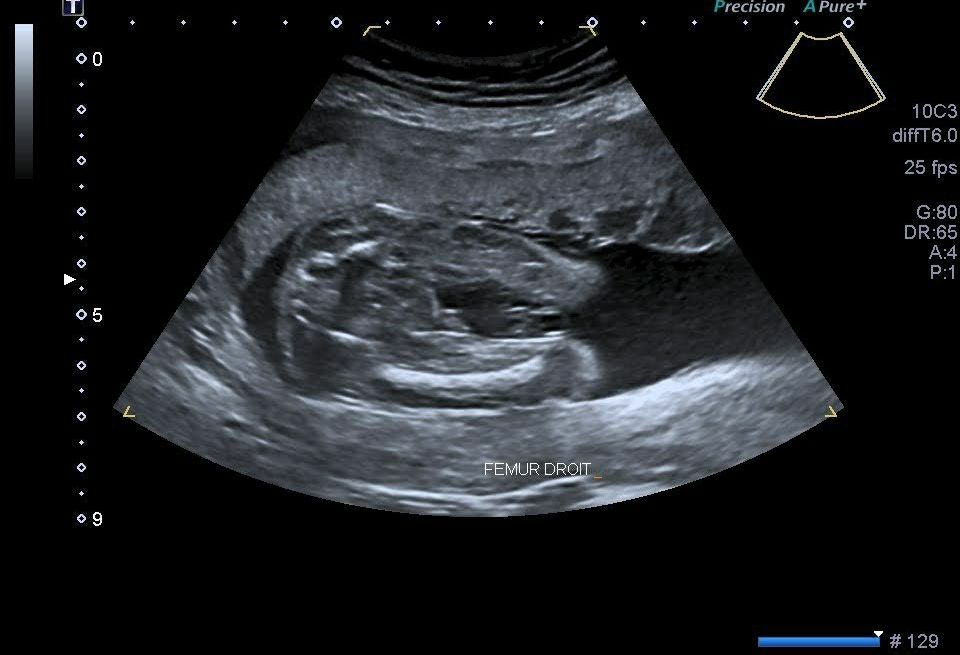

Пол ребёнка

Пол малыша

Кого вы видите на этом УЗИ? Мальчика или девочку?)

На втором фото вроде как мальчик, но где яички и если приблизить то видно как полоску половых губ))